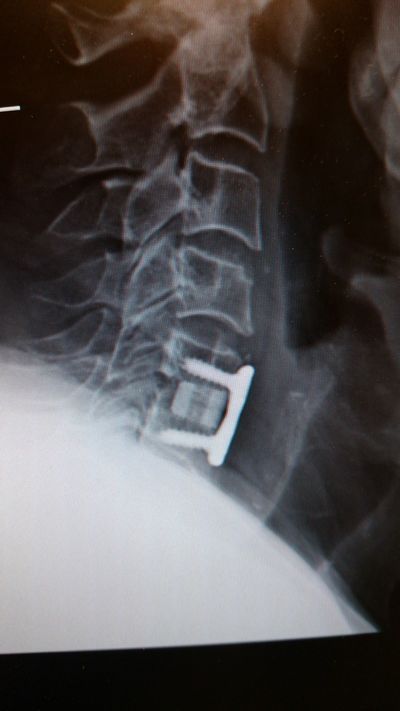

Dr. Morreale invented and pioneered the spine surgical procedure called Kyphofusion (also known as Kyfusion). This surgery can be done by way of either a traditional approach or a minimally invasive one. It is used for patients who would not be able to have surgery including elderly patients, patients with poor bone quality and cancer patients.